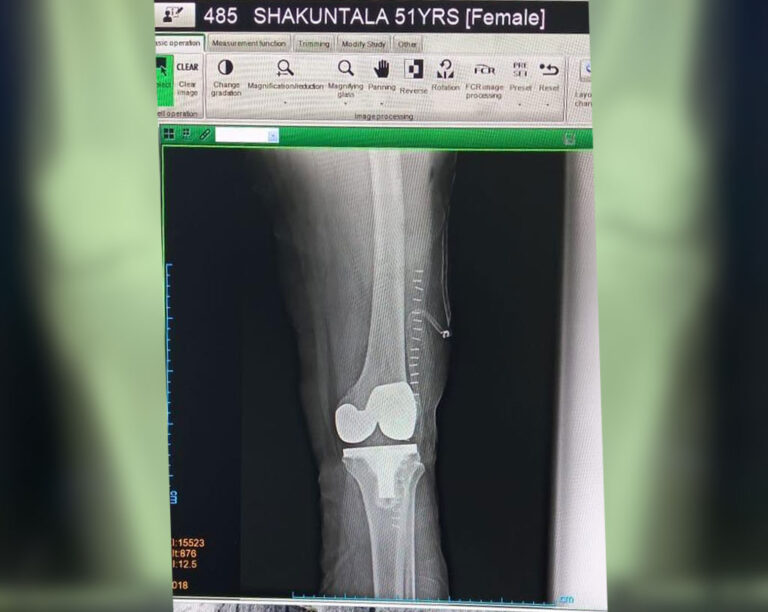

Total Knee Replacement

Name: Shakuntala

Date of Operation: 12 Mar 2021

Age: 52 Years

After Surgery